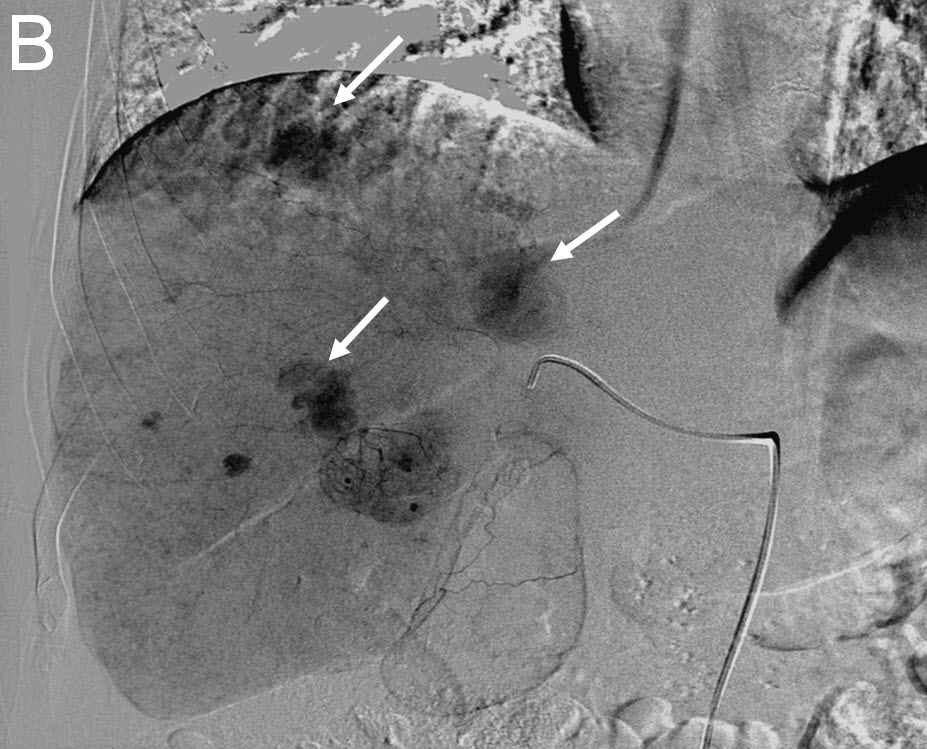

| (B) Delayed right liver angiogram showing multiple tumor "blushes" |